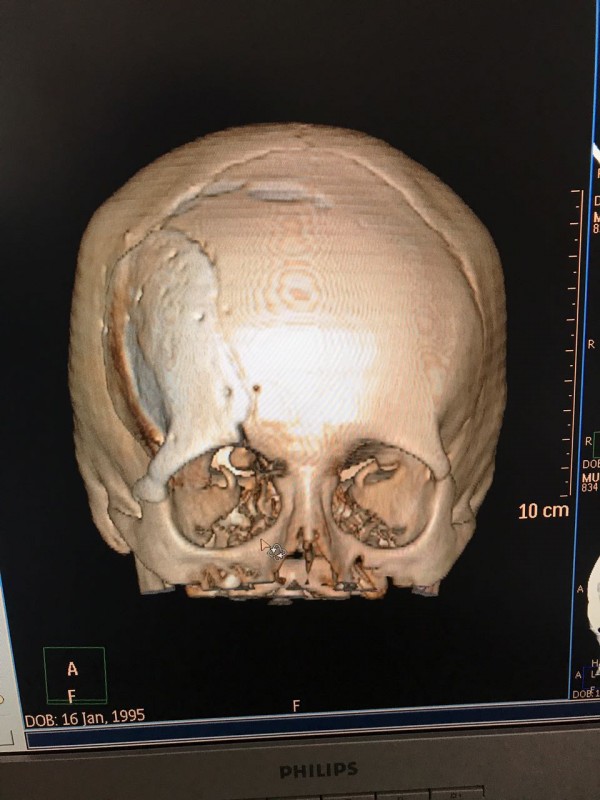

"Компьютерная томография показала, что костная опухоль поражала лобную кость и "крышу" орбиты глаза, которая, в свою очередь, сдавливала глазное яблоко. Чтобы убрать опухоль, потребовалось немало времени. Наша задача была сохранить глазное яблоко, зрительный нерв и сосуды. Если неправильно провести операцию и неправильно закрыть дефект, то в последующем это может привести к эстетической неполноте и асимметрии лица. Уникальность еще и в том, что в операции применялась 3D-стереолитография, которая делается только в Алматы", - рассказал он.

Снимок сделан до операции. Фото предоставлено Константином Ли